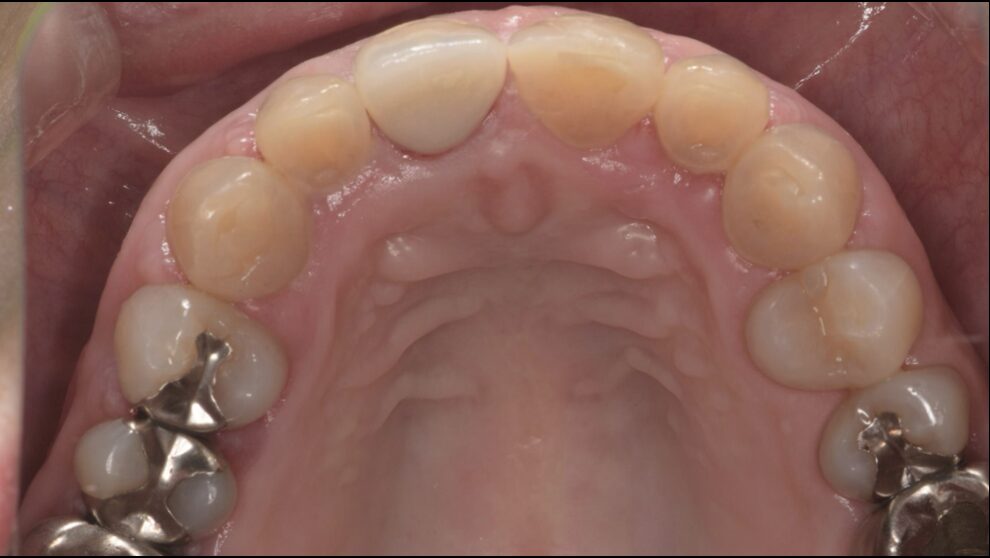

再根管治療を行い、セラミッククラウンSET後